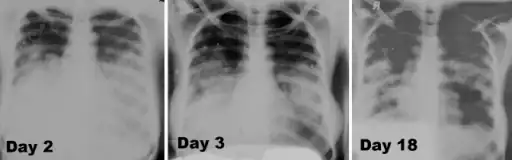

Image -primary pneumonic plague obtained on illness days 2, 3, and 18 shows bilateral lower lung zone predominant airspace disease associated with bilateral pleural effusions -

Chest x-ray of pneumonic plague showing bilateral, diffuse interstitial pleural infiltrates, and accompanying consolidation. As well as, what appeared to be marked, mediastinal adenopathy.